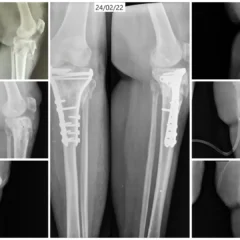

1️⃣ Open Reduction and Internal Fixation (ORIF)

Open reduction and internal fixation was performed for:

-

Fibula using plates and screws

-

Posterior malleolus using plates and screws

This ensured:

-

Accurate restoration of ankle alignment

-

Stable fixation of the lateral and posterior components

-

Proper joint congruity

2️⃣ Tension Band Wiring (TBW) for Medial Malleolus

The medial malleolus was stabilized using Tension Band Wiring (TBW) technique, which:

-

Converts tensile forces into compressive forces

-

Promotes stable bone healing

-

Provides strong fixation for small fracture fragments

The combined fixation approach restored full structural stability of the ankle joint.

Procedure Overview

| Condition | Right Trimalleolar Ankle Fracture |

|---|---|

| Main Procedure | Open Reduction and Internal Fixation (ORIF) |

| Fibula Fixation | Plates and Screws |

| Posterior Malleolus Fixation | Plates and Screws |

| Medial Malleolus Fixation | Tension Band Wiring (TBW) |

Outcome

With successful surgical fixation and dedicated physiotherapy, Mr. Shivkumar achieved:

-

Stable ankle alignment

-

Successful fracture healing

-

Progressive return to weight-bearing

-

Improved ankle mobility

-

Return to daily activities